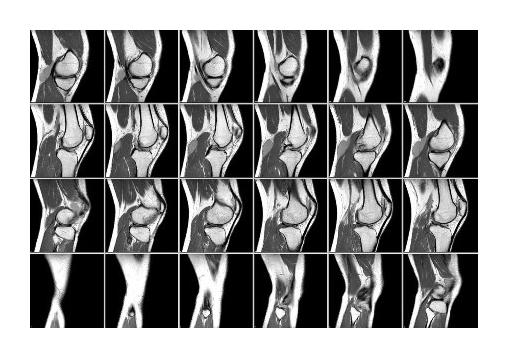

Изображение передается на монитор компьютера, где отображены послойные снимки локтя.

Современный мультиспиральный томограф позволяет получить трехмерную модель зоны исследования, если необходимо.

Все исследования могут выполняться с созданием 3D (трёхмерных) моделей и MPR реконструкцией.